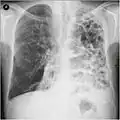

A chest X-ray is not useful to establish a diagnosis of COPD, but it is of use in either excluding other conditions or including comorbidities such as pulmonary fibrosis and bronchiectasis. Characteristic signs of COPD on X-ray include hyperinflation (shown by a flattened diaphragm and an increased retrosternal air space) and lung hyperlucency.[5] A saber-sheath trachea may also be shown that is indicative of COPD.[111]

Lung bulla as seen on chest X-ray in a person with severe COPD

A severe case of bullous emphysema -